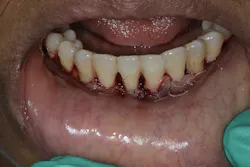

- Ensure tooth does not have a root fracture and check/refer for endodontic treatment if tooth is nonvital (figure 1)

- Splint tooth and adjust occlusion11 (figure 2)